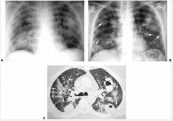

Viêm phổi là một bệnh nhiễm trùng phổi phổ biến gây ra bởi vi khuẩn, virus hoặc nấm. Bài viết này sẽ nói rõ về bệnh lý viêm phổi nocardiosis ở người ghép thận. Mời các bạn tham khảo!

Viêm phổi là một trong những bệnh nhiễm trùng cơ hội nghiêm trọng nhất đối với những người nhiễm HIV. Tần suất viêm phổi do Pneumocystis trên người nhiễm HIV ở giai đoạn AIDS là rất cao. Cùng eLip tìm hiểu rõ hơn với những thông tin dưới bài viết nhé!

Viêm phổi bệnh viện là viêm phổi xảy ra sau 48 giờ nhập viện mà trước đó không có triệu chứng hô hấp hay nhiễm trùng và không có tổn thương mới hay tiến triển trên X quang ngực trước 48 giờ nhập viện. Để hiểu rõ hơn về hội chứng này, mời các bạn cùng tham khảo bài viết dưới đây nhé!